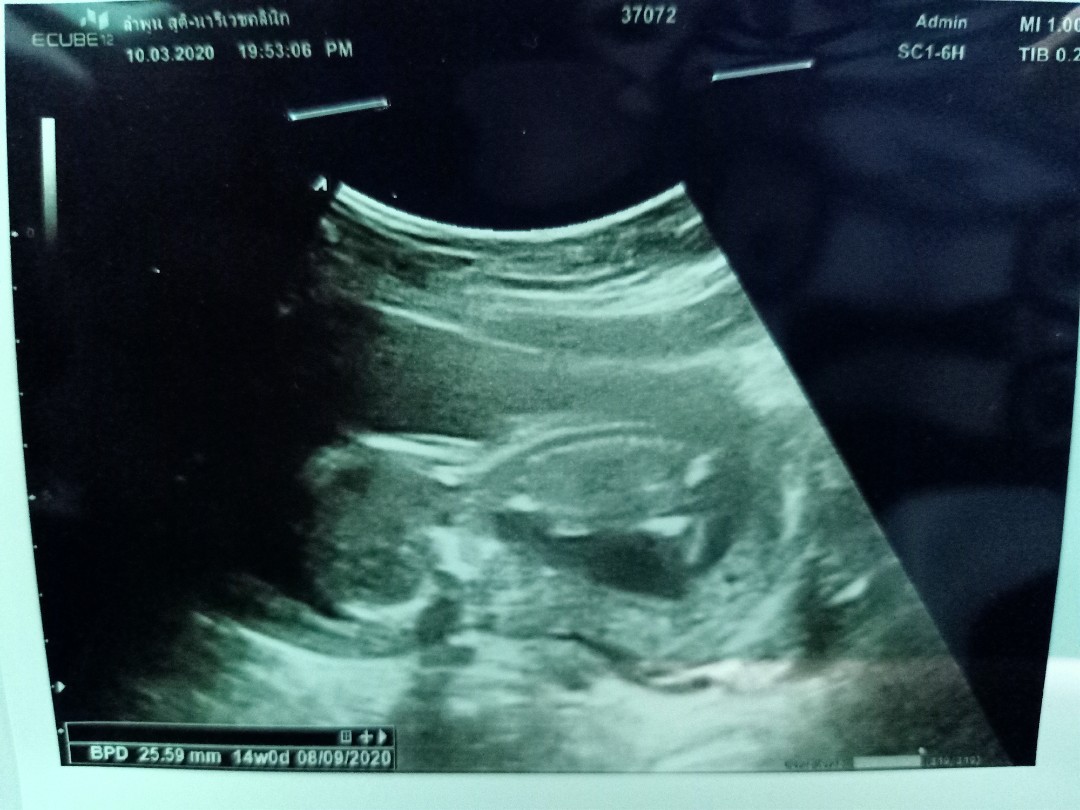

14W ค่ะ น้องนอนคว่ำ